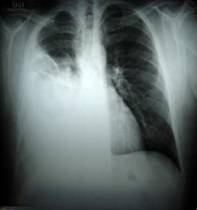

- Radiografía del tórax: radiografía de los órganos y huesos del interior del pecho.